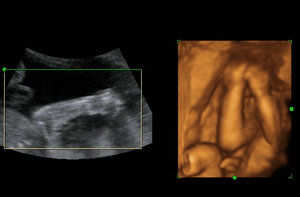

【哈尔滨玛丽亚妇产医院引入先进的四维彩超设备 保障女性孕期胎儿安全】

哈尔滨玛丽亚妇产医院对于孕期女性可以提供专业的孕期检查项目,先进的四维彩超设备帮助孕妈妈进行排畸检查,提前感受到小宝宝的生命力。而且我院自建院以来一直都很坚持“与世界先进医疗同步”的医疗理念,典雅时尚大气的候诊大厅区域,温馨私密性的独立诊室和舒适洁净的家庭式病房,以及具备符合国际标准的优质陪护服务,努力打造成为具有现代医学前沿和鲜明特色的专家型的医院。